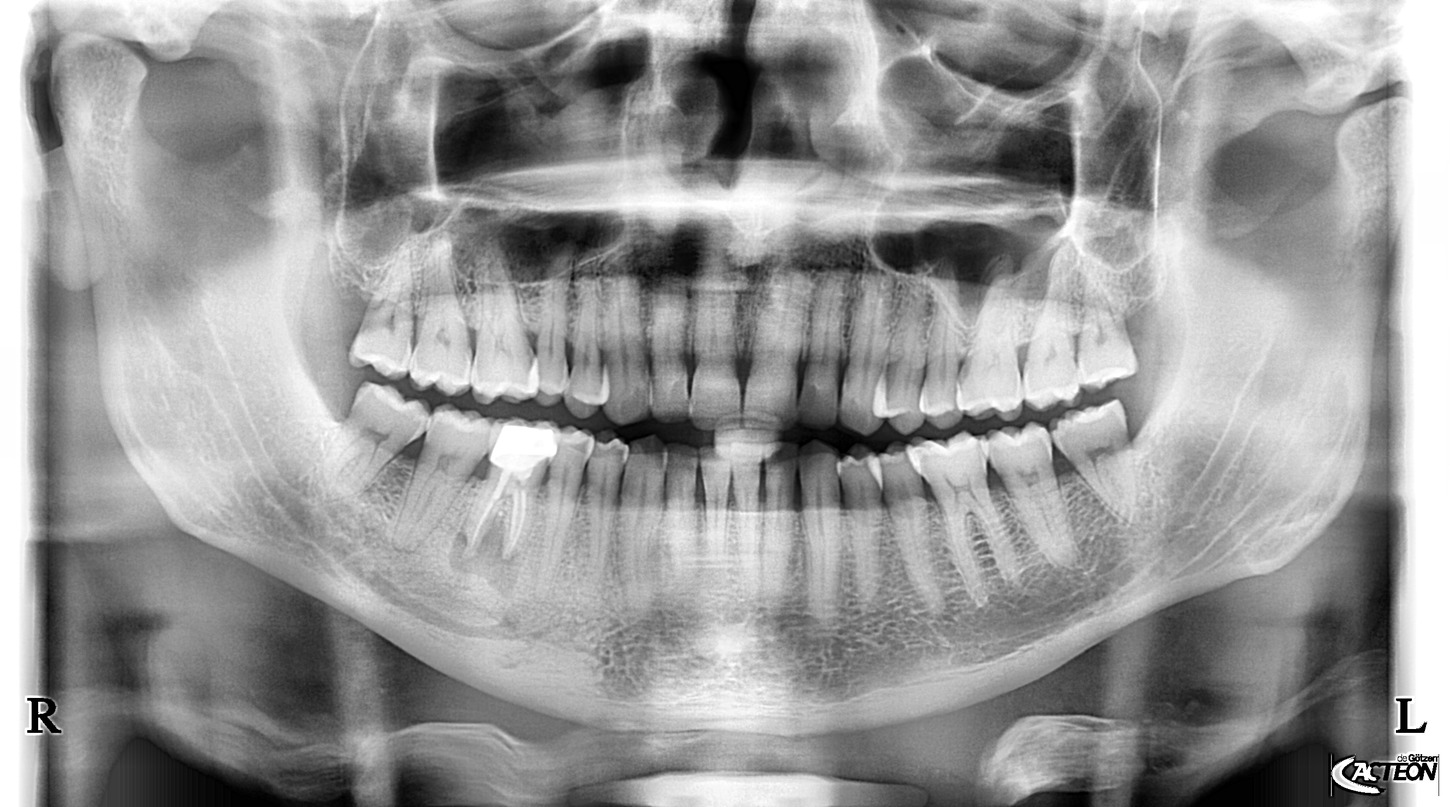

Přesné snímky pro zlepšení diagnostiky. To přináší panoramatické RTG od dodavatele Acteon Satelec, které jsou svými parametry a cenovou dostupností nejlepší volbou pro stomatologické praxe. Volit můžete z mnoha variant (kotvení, rozšiřitelnost o 3D, rozšiřitelnost o kefalometrické rameno atd.) a tím jsou snadno přizpůsobitelné do každého prostoru a každé stomatologické praxe. Jedná se o OPG, která svou kvalitou a ovládáním předčí všechna očekávání a řadí se tak mezi nejpoužívanější OPG na světovém i českém trhu. Poskytuje veškeré panoramatické možnosti pro všeobecnou stomatologii: dentální panoramatickou, klouby i sinusy. Jednoduché nastavení, pohodlí pacienta a rychlé vyšetření. Společnost Fénix Dental dodává všechny přístroje s odborným zaškolením, a to dle individuální potřeby každého uživatele. Díky Aies SW je zobrazení OPG snímků bezkonkurenční. Díky panoramatickému RTG od výrobce Acteon, získáte nejpřesnější diagnostickou hodnotu, která snese i ta nejpřísnější měřítka. Společnost Fénix Dental je přímý zástupce a autorizovaný servis pro produkty Acteon. Prohlédněte si naši nabídku právě zde a neváhejte nás kontaktovat pro bližší informace.